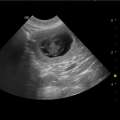

Heute ganz früh schon hatten wir den Ultraschalltermin bei unserer Tierärztin. Wie immer waren wir natürlich etwas aufgeregt. Hatte uns unser Eindruck getrogen oder dürfen wir uns auf Babies freuen? Und dann dieser Moment, wenn man das erste kleine Herzchen schlagen sieht und noch eins und noch eins und ... unbeschreiblich dieses Gefühl: man will weinen, lachen, tanzen, singen und es der ganzen Welt erzählen. Auf eine genaue Anzahl wollte sich die Ärztin nicht festlegen, aber es ist einiges los in unserer Dyvke.